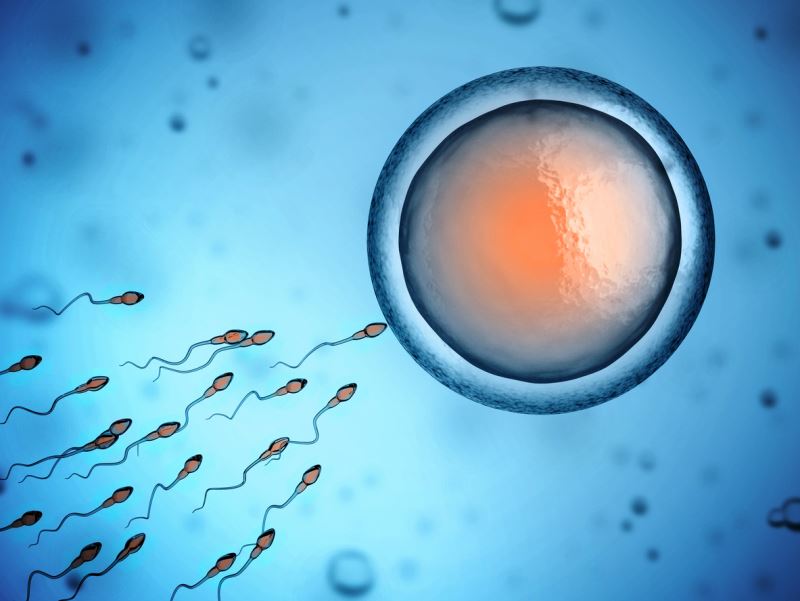

yumurtalıklarını aldıran kadınları duymuştum ama ben yumurta üretmeye yarayan şeyi aldırdıklarını sanıyordum bu güne kadar. ben her seferinde lazım oldukça yani ayda bir kere kadında bir yumurta üretilip bırakılıyor sanıyordum. halbuki o yumurta zaten en başından beri orda duruyor sırasını bekliyor ve her ay ordan bir yumurta döllenmek için en kaliteli olan yumurta bırakılıyormuş.

kadının yaşı 35'i geçmeye başladıktan sonra, elinde daha az kaliteli yumurta kaldığı için kadının gebe kalması bu yüzden giderek zorlaşıyormuş. yani kadının doğum için yaşının geçiyor olmasının temel sebebi buymuş.

bu seçimin mantığı şu: şimdi olgunlaşmak isteyen yumurta fsh hormonunu kullanmak zorunda. (ovülasyon: olgunlaşan yumurtanın keseyi yırtarak tüplere atılması ve orada spermle döllenmeyi beklemesi) ovülasyondan önce bu fsh hormonu azalıyor. çünkü düşük fsh düzeylerinde bile hormonu kullanabilip kendini olgunlaştırabilen sadece bir yumurta oluyor. yoklukta bile hayatta kalabilen yumurta övülasyon ile tüplere atılmayı hakeden yumurta yani çocuk adayı oluyor. seçilim bu şekilde yapılıyor. tüplerde döllenmeyi bekleyen yumurta ise spermle karşılaşmazsa dışarı atılıyor(menstruasyon) bir kadın hayatı boyunca ortalama 400 kere adet görür böylece 400 kere gebe kalabilme potansiyeli vardır kağıt üzerinde. güçlünün hayatta kalmasına dair güzel bir fizyolojik olay"